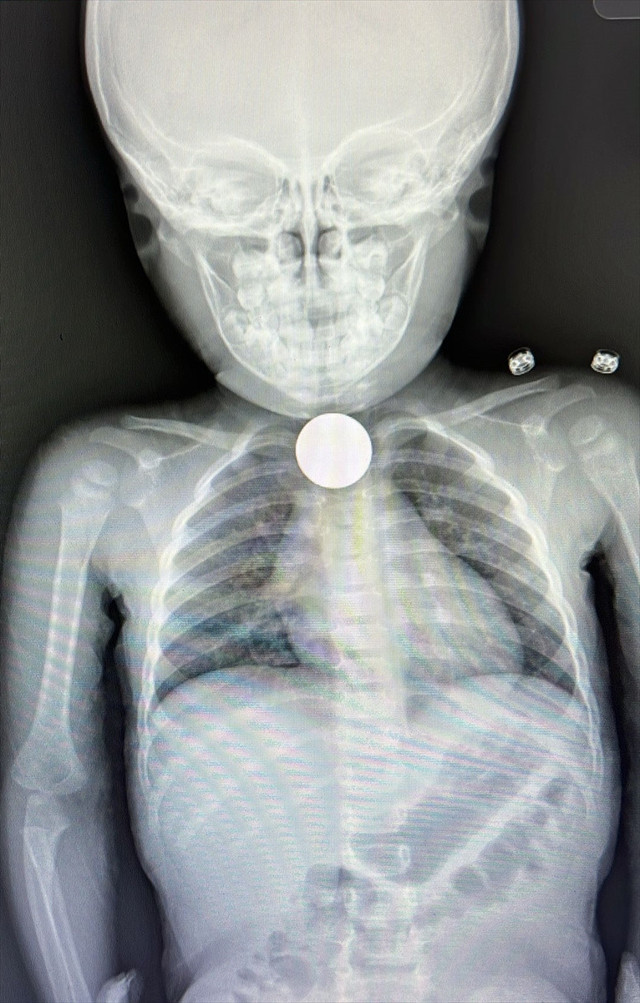

Burada yapılan detaylı tetkiklerde çocuğun yemek borusunda madeni para görüldü. Her geçen dakika durumu daha da kötüleşen İkra'nın yemek borusunu tıkayan para, başarıyla çıkarıldı.

Tıbbi müdahalenin ardından çocuk yutkunmaya ve rahat nefes alıp vermeye başladı, şikayetleri sona erdi.